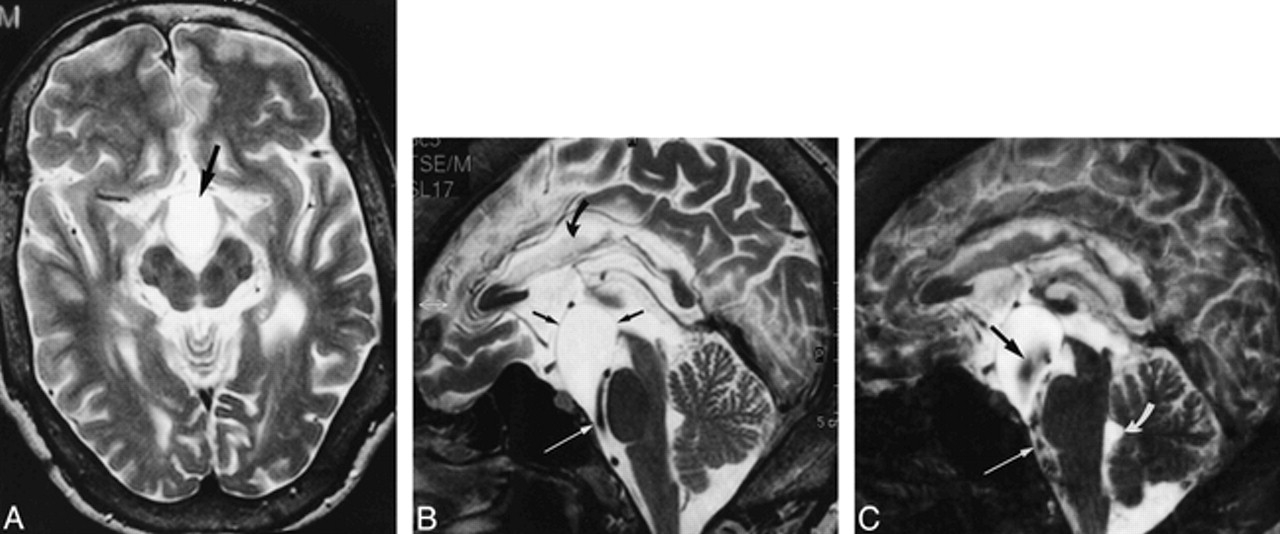

28-year-old man with a prepontine arachnoid cyst, corpus callosum anomaly, hydrocephalus, ventriculoperitoneal shunt, and headaches.

A, T2-weighted axial image (2000/80/1) shows a hyperintense cyst (arrow) within the prepontine cistern, pushing the crura cerebri and the optic chiasm apart.

B, Midsagittal T2-weighted section (2000/80/1) shows defined margins of the cyst (straight black arrows), except for the narrowing between the basilar artery and skull base (white arrow). Note callosal dysplasia (curved arrow). The bottom of the third ventricle is elevated.

C, Midsagittal SSFP image (20/25/1) reveals broad-based signal void within the cyst (black arrow) probably due to transmission of pulsations from the basilar artery. A continuous jet phenomenon between the prepontine cistern with pronounced signal void (straight white arrow) on the one hand and the cyst on the other hand is not demonstrable, making communication unlikely. Flow void within the fourth ventricle was absent (curved arrow) owing to occlusion of the aqueduct. Membranectomy was not performed, because the patient had no evidence of visual impairment.